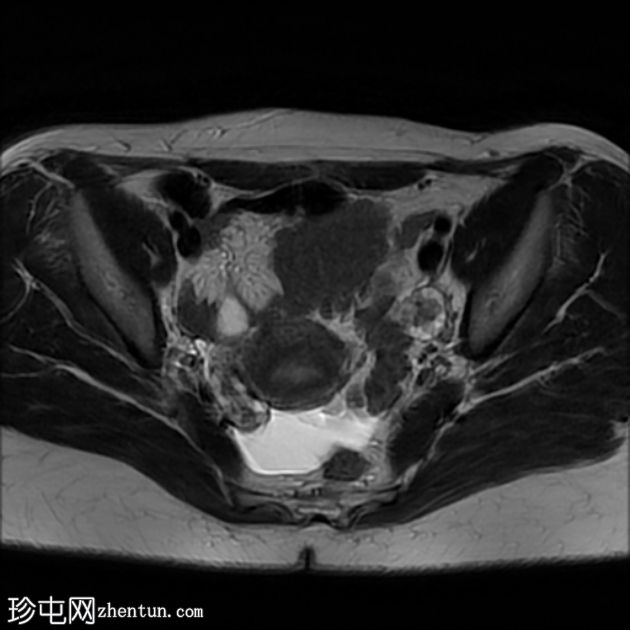

T2加权像

轴位

肝脏肿大,可见多发性双叶肝囊肿。

脾脏肿大,可见多发性大囊肿,内层脱离。

肝脾包虫囊肿的典型

影像

学表现。